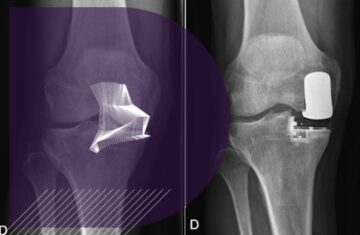

prothese unicompartimentale du genou chirurgie genou paris clinique drouot

Quelle est la durée de vie d’une prothèse unicompartimentale ?

prothese unicompartimentale genou convalescence chirugien genou paris clinique drouot

Prothèse unicompartimentale de genou : quelle convalescence ?